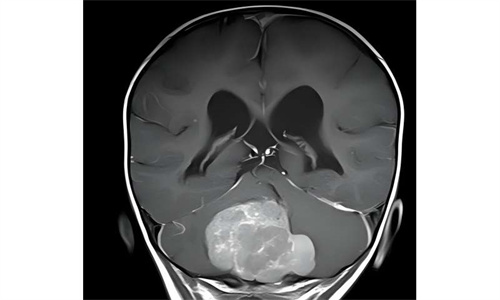

髓母细胞瘤是儿童最常见的实体瘤之一,也是儿童最常见的恶性脑肿瘤。肿瘤生长在小脑,随着肿瘤的生长,会损害重要的大脑中枢。基于组织特征和遗传标准,髓母细胞瘤现在被分为不同的风险组,可以采取完全不同的过程。虽然某些亚型进展迅速并形成转移,但也有其他形式通常可以通过手术、化疗和放疗的强化综合治疗来治愈。

一组研究人员现在使用一种新方法来研究是什么在细胞水平上将某些肿瘤导向更良性或恶性的方向。一种类型的髓母细胞瘤以其良好的恢复机会为特征,同时以其组织的特殊结构特性为特征,作为它们的模型:在所谓的具有广泛结节的髓母细胞瘤(MBEN)中,小的组织室被界定在肿瘤内,它们以葡萄状方式连接。

研究表明,位于这些结节中的肿瘤细胞不再活跃分裂,其遗传程序与成熟脑细胞相似。然而,在中间区域,科学家们确定了不同的细胞类型:除了免疫和结缔组织细胞,还有明显更具侵略性的肿瘤细胞,它们继续不受控制地分裂,其遗传程序与快速生长的髓母细胞瘤和未成熟的神经细胞更相似。然而,在它们迁移到淋巴结的过程中,癌细胞成熟回到神经样细胞,并且不再分裂。